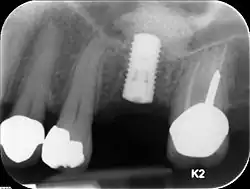

Analog dem Knochenabbau durch Parodontitis kann sich auch das Implantatbett entzünden, was zu einer Periimplantitis mit Knochenabbau um das Implantat herum führen kann. Nach einer Explantation (Entfernung) eines solchen Implantats muss meist der Knochen wieder aufgebaut werden.

Im Unterkiefer ist die Höhe des Kieferknochens nach kaudal durch den Nervus mandibularis begrenzt. Dieser darf nicht tangiert werden, weil es sonst zu bleibenden Sensibilitätsausfällen insbesondere im Bereich der Unterlippe und des Kinns kommen kann. Die Mindestlänge eines Implantats beträgt 8 mm, wobei Implantatlängen von 10 bis 12 mm angestrebt werden. Reicht diese Höhe nicht aus, muss ein Knochenaufbau durchgeführt werden. Ähnliches gilt für einen nicht ausreichend breiten Kieferkammknochen, in den das Implantat eingebracht werden soll.